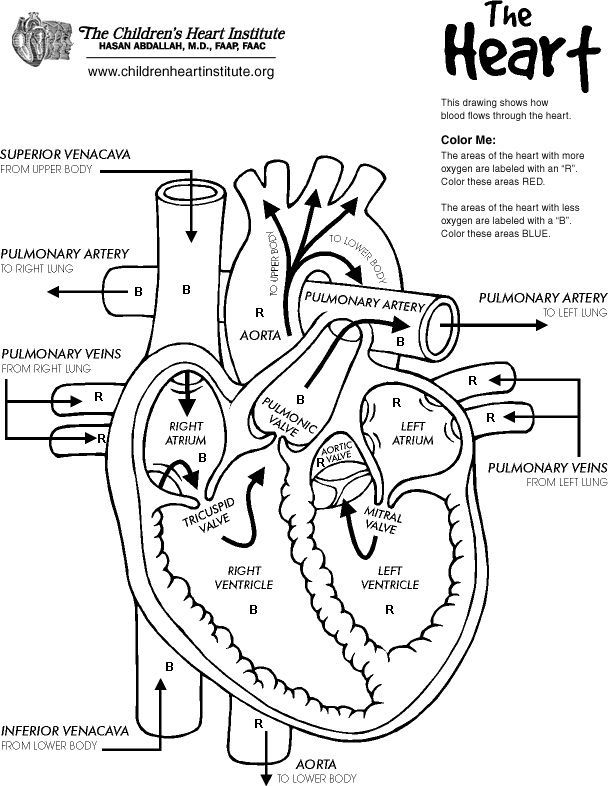

921x690 Anatomical Heart Coloring Pages

620x875 Anatomy Coloring Pages Heart

2550x3300 Anatomical Heart Coloring Page

608x786 Anatomy Of The Heart Coloring Pages Heart Anatomy Coloring Pages

600x848 Healthy Heart In Human Anatomy Coloring Pages Bulk Color

600x450 Heart Anatomy Coloring Pages Heart Anatomy Coloring Pages